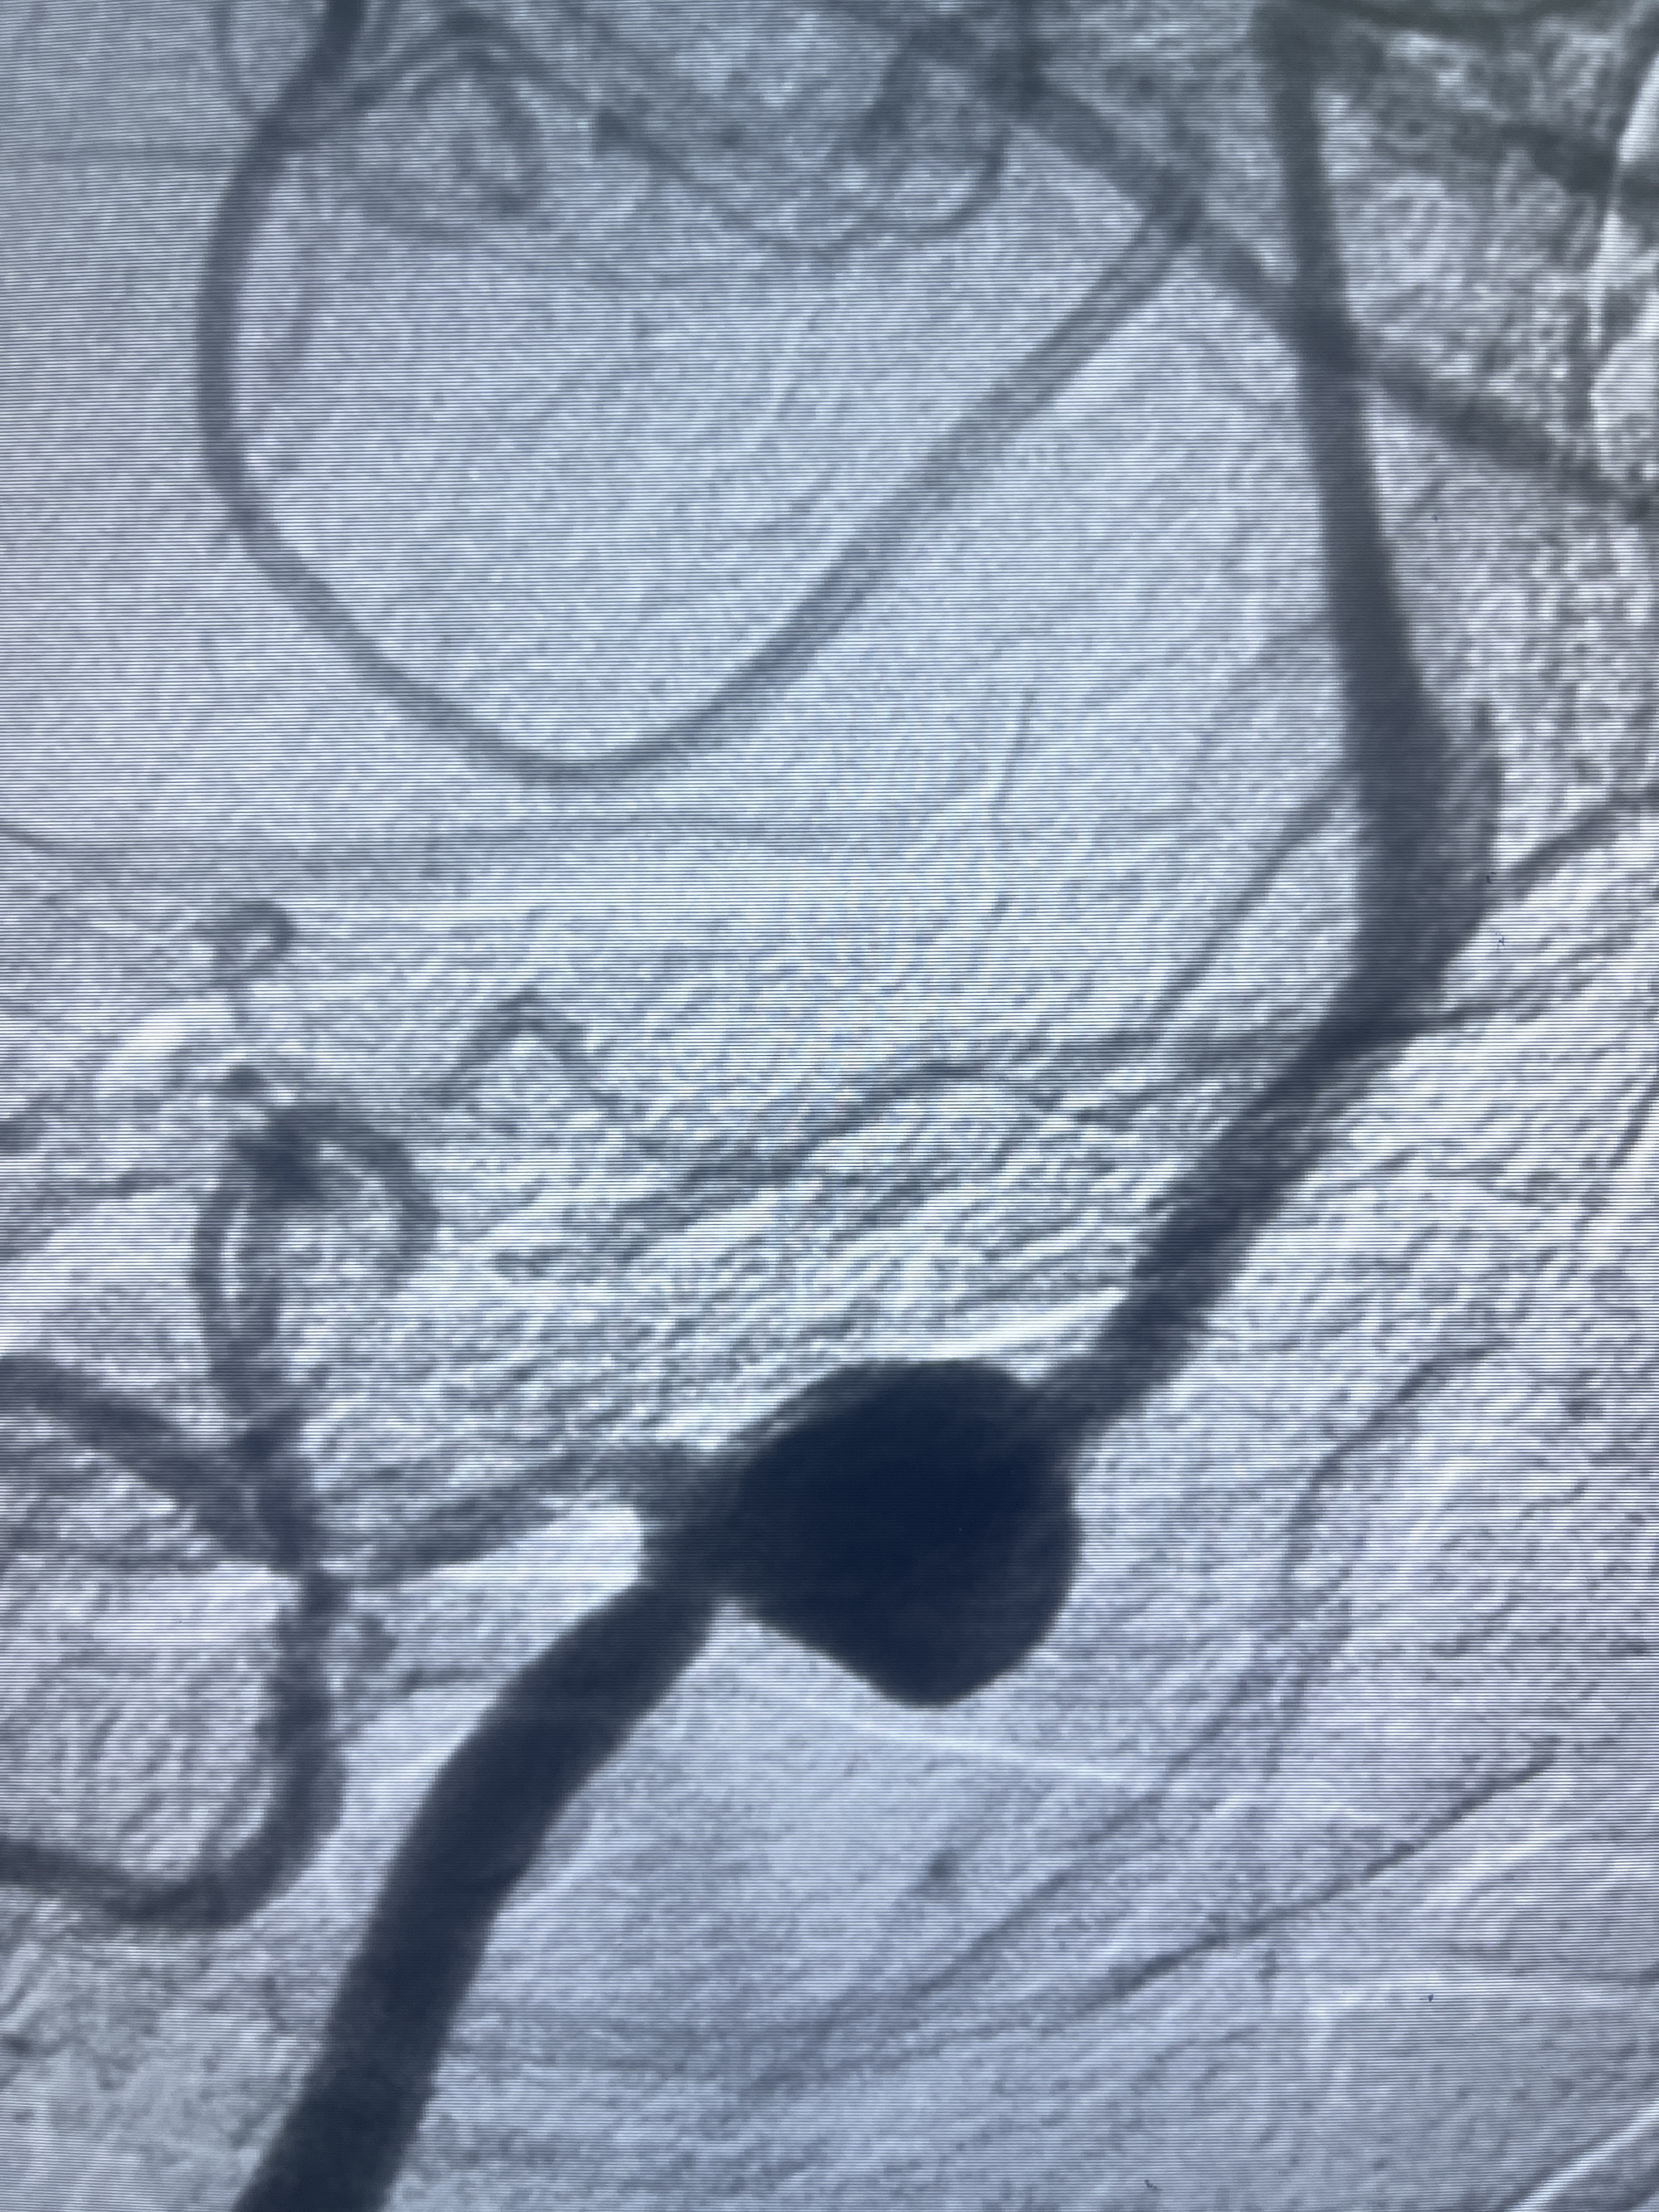

202.04.28脑血管造影:右侧大脑后动脉远段闭塞,右侧椎动脉V4段可见“囊状造影剂填充影”,大小7.64*7.65mm,可见PICA由动脉瘤发出;